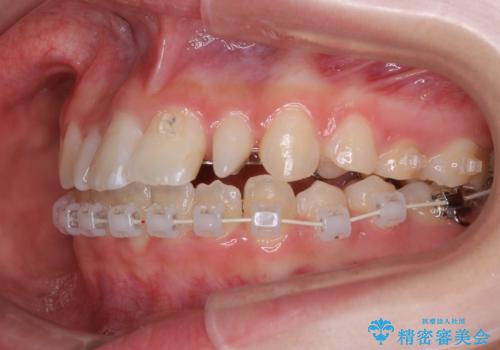

- 矯正装置

- ハーフリンガル

- ハーフリンガルシステムによる矯正治療を行いながら、スペースコントロールをみて前歯を仮歯へ

→矯正の終了をメドに仮歯をセラミックへ置き換える